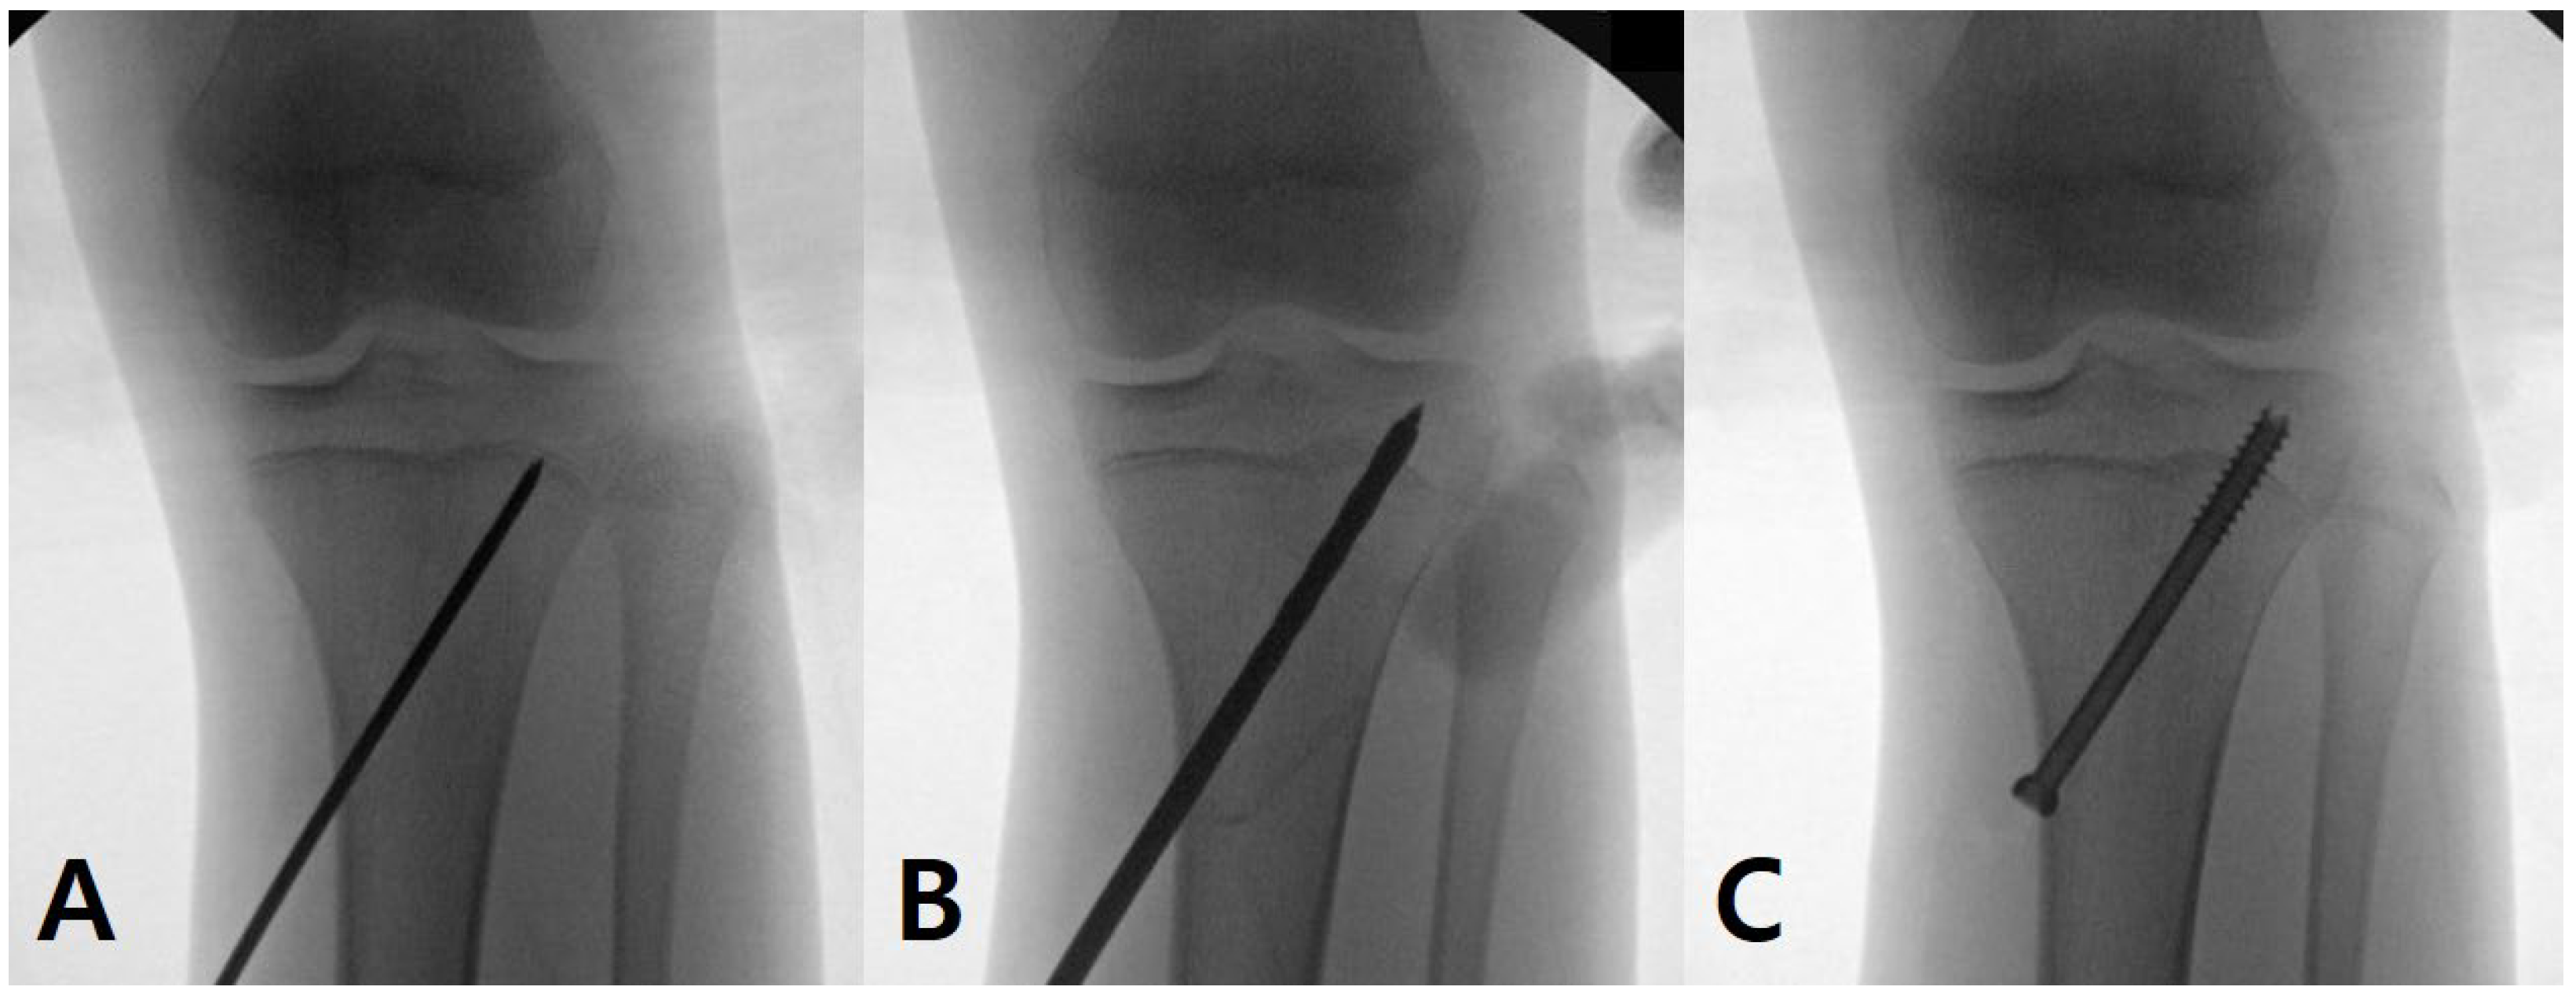

2.2. Surgical Technique